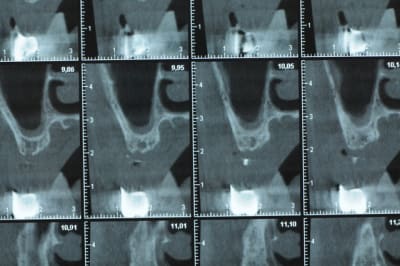

Une petite étude de ton cas D57

Sous réserves bien sur de voir l’animal en vrai

Les zones exploitables radiologiquement parlant:

Coupes implant

2,3 40100

4,96 35130 avec sinus lift mais difficile

5,25 35150

6,02 35130

6,78 35115 après réduction de hauteur de crête

7,26 35115 après réduction de hauteur de crête

8,51 35150

10,43 40115 ou 50115

11,10 40115

Ce qui nous fait 9 implants possible évidement avec un comblement de sinus on augmenterait encore les zones implantable mais ce n’est pas le but recherché, avec 8 (4+4) il doit être possible de faire une belle barre support de complet